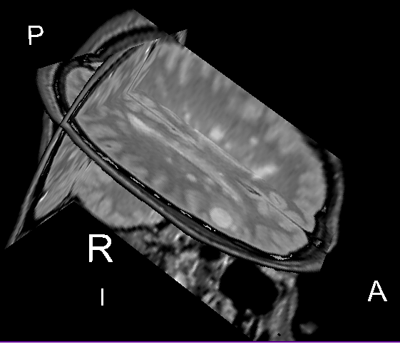

Slicer Registration Library Case 04: Intra-subject Brain MR of Multiple Sclerosis: Multi-contrast series for lesion change assessment

This scenario occurs in many forms whenever we wish to assess change in a series of multi-contrast MRI. The follow-up scan(s) are to be aligned with the baseline, but also the different series within each exam need to be co-registered, since the subject may have moved between acquisitions. Hence we have a set of nested registrations. This particular exam features a dual echo scan (PD/T2), where the two structural scans are aligned by default. The post-contrast T1-GdDTPA scan however is not necessarily aligned with the dual echo. Also the post-contrast scan is taken with a clipped field of view (FOV) and a lower axial resolution, with 4mm slices and a 1mm gap (which we treat here as a de facto 5mm slice).

reference/fixed : PD baseline exam , 0.9375 x 0.9375 x 3 mm voxel size, axial acquisition, RAS orientation.

reference/fixed : T2 baseline exam , 0.9375 x 0.9375 x 3 mm voxel size, axial acquisition, RAS orientation.

moving: T1-GdDTPA baseline exam 0.9375 x 0.9375 x 5 mm voxel size, axial acquisition.